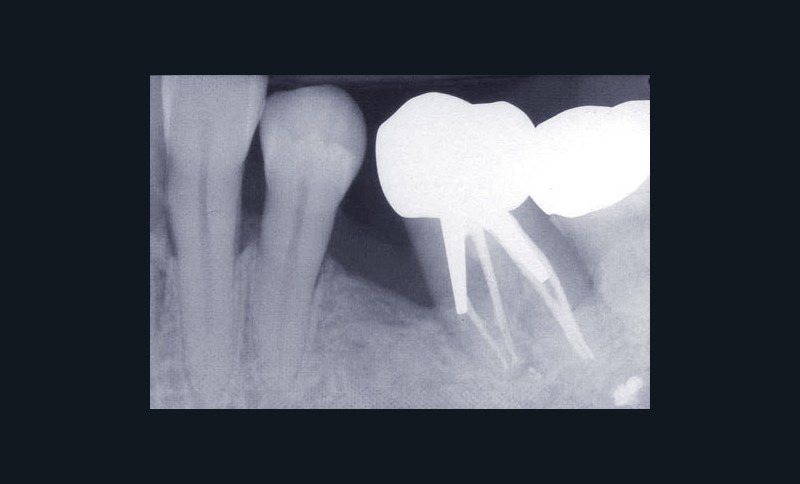

Les examens cliniques et radiographiques montrent une parodontite chronique généralisée (fig. 1a à m).

Nous décidons d’entreprendre une thérapeutique initiale parodontale classique dans tous les secteurs, y compris l’extraction de 24, un bridge de 45 à 48 avec 46 en pontique, un bridge complet de contention de 17 à 27 sur 11 piliers dentaires et une greffe épithélio-conjonctive sur 31. Cette dernière ne sera jamais réalisée. Le bridge maxillaire permettra de réduire le surplomb antérieur et d’améliorer le sourire de la patiente, ce qui constitue l’une de ses demandes.